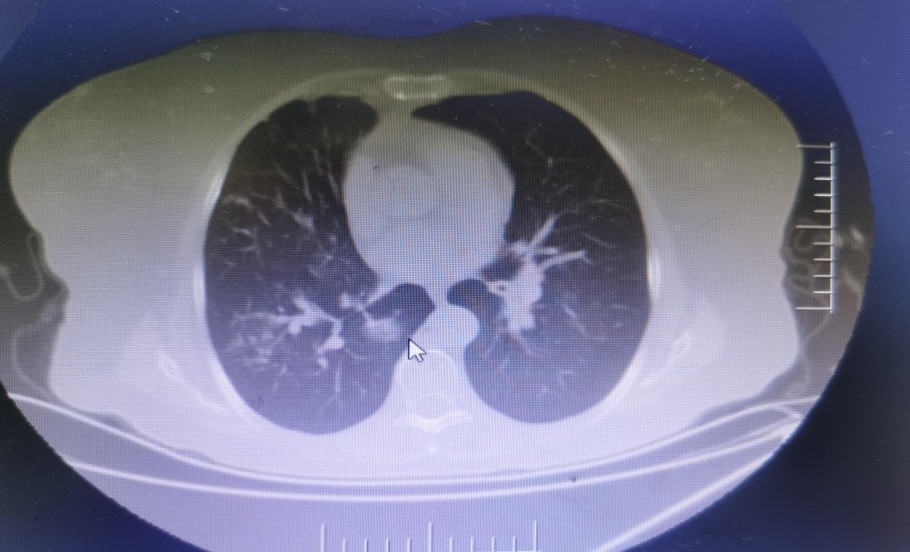

病例一:72岁的曾女士,因反复咳嗽、喘息、气促30年,加重2+月于6月27日入院。查体: 体温:36.7℃ 脉搏:90次/分,呼吸:22次/分,血压:126/79mmHg。全身浅表淋巴结未扪及肿大。口腔内见少许真菌斑。胸廓对称呈桶状,肋间隙增宽,双肺叩诊为过轻音,双肺呼吸音低,闻及大量哮鸣音,双下肺闻及少许湿啰音。入院诊断:1.慢性阻塞性肺疾病急性加重期; 2.双肺支气管扩张伴感染;3.慢性肺源性心脏病(失代偿期)。胸部CT:右肺下叶内基底段亚实性结节,最大横截面约2.0cm*1.4cm,边缘可见血管影(如图所示)

经过几位专家的认真分析讨论,认为该病人肺癌可能性大,因病人肺功能差,慢阻肺严重,不能耐受胸腔镜手术治疗。建议肿瘤科行穿刺活检,诊断明确后可行射频消融术等保守治疗。

该病人经肿瘤科穿刺证实为肺微浸润腺癌,行射频消融术,手术顺利。